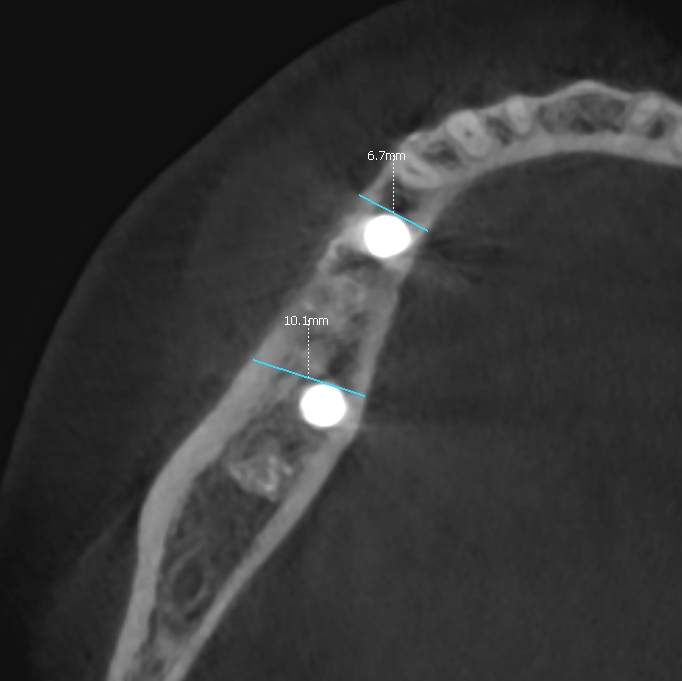

Ryc. 12. Skan tomografii stożkowej w okolicy 45, w 10 dobie po zabiegu.

Po okresie 6 miesięcy wykazano prawidłową resorpcję cementu i regenerację wyrostka poprzez odtworzenie kości żywiciela (pacjenta) do szerokości około 8 mm (ryc.13).

Ryc. 13. Regeneracja blaszki korowej przedsionkowej i deficytu kości w okolicy 45-46 6 miesięcy po zabiegu.

Regenerację blaszki przedsionkowej potwierdzono także klinicznie po odwarstwieniu płata podczas zabiegu planowej implantacji. Zmierzono szerokość wyrostka na poziomie 7-8 mm (ryc.14). Po wyrównaniu płaszczyzny wyrostka (ryc. 15) wykonano łoża dla implantów śrubowych w okolicy 45 (dł. 10 mm, śr. 3.7 mm) i 46/47 (dł. 10 mm, śr. 4.1 mm) (ryc.16), które wprowadzono w kość z momentem obrotowym około 25 Ncm. Ranę zaopatrzono szwami (PTFE – politetrafluoroetylen 4-0, igła odwrotnie tnąca, profil 3/8 koła długość 16 mm) (ryc.17).

Ryc. 20. Skan w płaszczyźnie horyzontalnej ukazuje regenerację blaszki korowej przedsionkowej